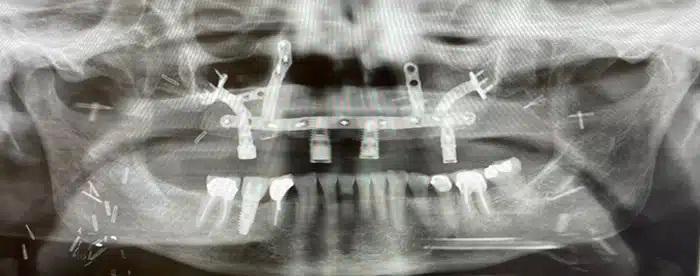

Specialized hardware and dental implants were created and inserted as part of Sue’s reconstructive surgery procedure.

The next step would focus on the reconstruction and rebuilding of her upper jaw using a free tissue transfer, or free flap. The procedure involved the transplant of the fibula bone, skin, and blood vessels from the lower leg to reconstruct the upper jaw and palate. Specialized hardware was also designed to hold the transferred tissue in place, plus dental implants for adding a prosthesis for the replacement of Sue’s teeth.

With the assistance of Nagi Demian, DDS, MD, professor and Thomas M. Weil Professorship in Oral and Maxillofacial Surgery at UTHealth Houston School of Dentistry, intraoperative navigation techniques were utilized to ensure the reconstruction went exactly as planned, allowing for the placement of the dental implants created for Sue’s new teeth.